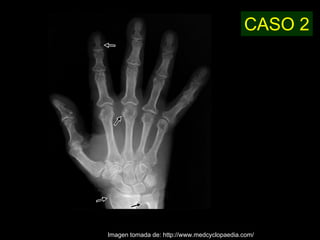

Este documento describe la acromegalia, una condición causada por un exceso de hormona de crecimiento producida por la hipófisis. Provoca un crecimiento anormal de las extremidades, la cara y los órganos internos. Sus síntomas incluyen prominencia de la mandíbula, las manos y los pies, así como engrosamiento de la piel y huesos. Generalmente se debe a un adenoma de la hipófisis y su diagnóstico se realiza mediante pruebas de sangre y resonancia magnética.